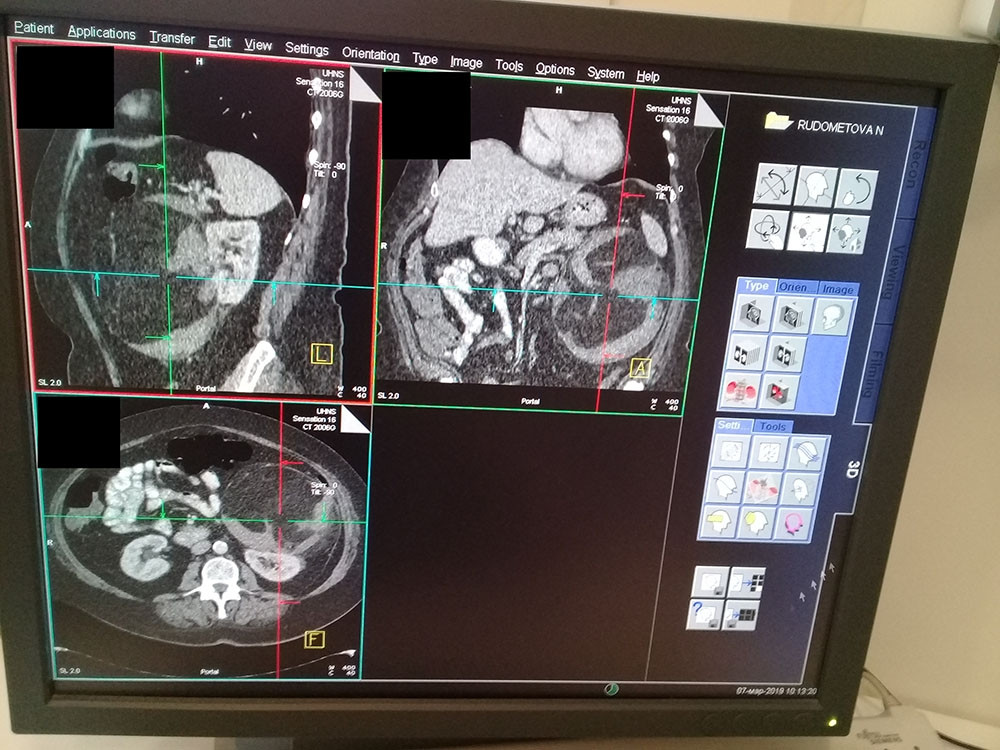

КТ-картина липоматозного образования в передних отделах забрюшинного пространства слева, связанное с передней поверхностью левой почки - больше данных за наличие крупной экстраренальной ангиомилипомы, с категоричностью не исключается липосаркома.